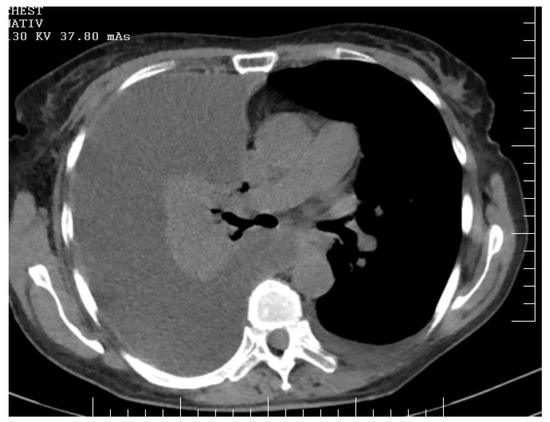

Successful Implementation of HITOC and HIPEC in the Management of Advanced Ovarian Carcinoma with Pleural and Peritoneal Carcinomatosis

Moldovan, B.; Saon, C.T.; Adam, I.-I.; Pisica, R.-M.; Silaghi, V.T.; Untaru, V.; Stoica, D.; Crisan, M.; Popianas, A.; Pescaru, F.; et al. Successful Implementation of HITOC and HIPEC in the Management of Advanced Ovarian Carcinoma with Pleural and Peritoneal Carcinomatosis. Diagnostics 2024, 14, 455. https://doi.org/10.3390/diagnostics14050455